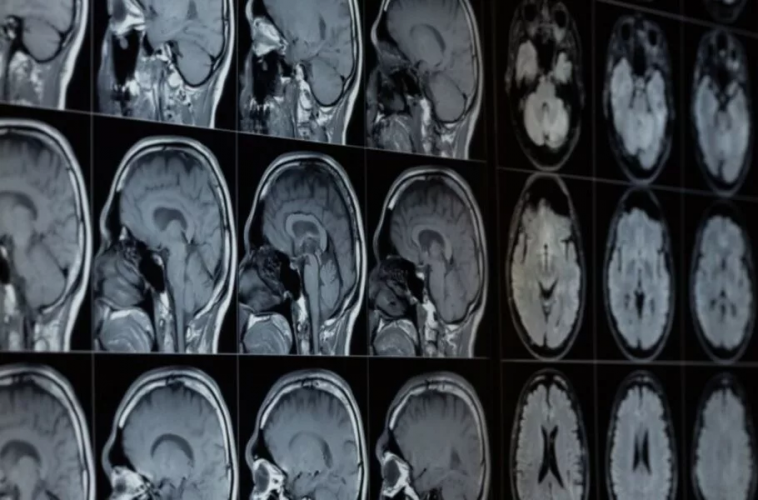

براساس اعلام رسمی مایکروسافت، این شرکت هوش مصنوعی جدیدی را توسعه داده است که میتواند برای آنالیز تصاویر پزشکی کاربرد داشته باشد. این ابزار هوش مصنوعی جدید BiomedParse نام دارد. از این ابزار میتوان برای ارزیابی سیتیاسکن، امآرآی، تصاویر اشعه ایکس، اولتراسوند و انواع دیگر تصاویر پزشکی برای شناسایی مشکلات احتمالی یا تشخیص انواع سلولها یا سایر پدیدههای بیولوژیکی در یک تصویر استفاده کرد و میتواند در تشخیص سرطان به پزشکان کمک کند.

به گفته مایکروسافت، پزشکان برای استفاده از این ابزار لازم است ابتدا متنی را به آن بدهند؛ برای مثال، پزشکان میتوانند عبارت «سلولهای پاتولوژیک» را تایپ کنند و هوش مصنوعی محل قرارگرفتن آنها در تصویر را شناسایی میکند و تاکنون توانسته مواردی همچون تومورها، ملانوم، ادم سیستوئید ماکولا، عفونت قفسه سینه کووید ۱۹ و گلیوما مغز و سایر بیماریها را شناسایی کند.